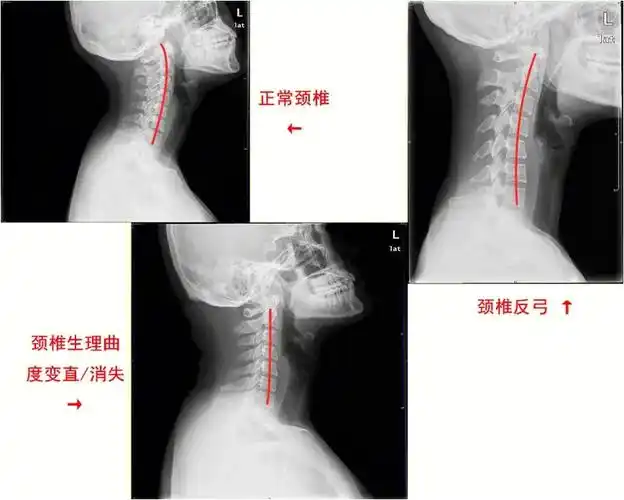

颈曲变直拿什么拯救你我的颈椎